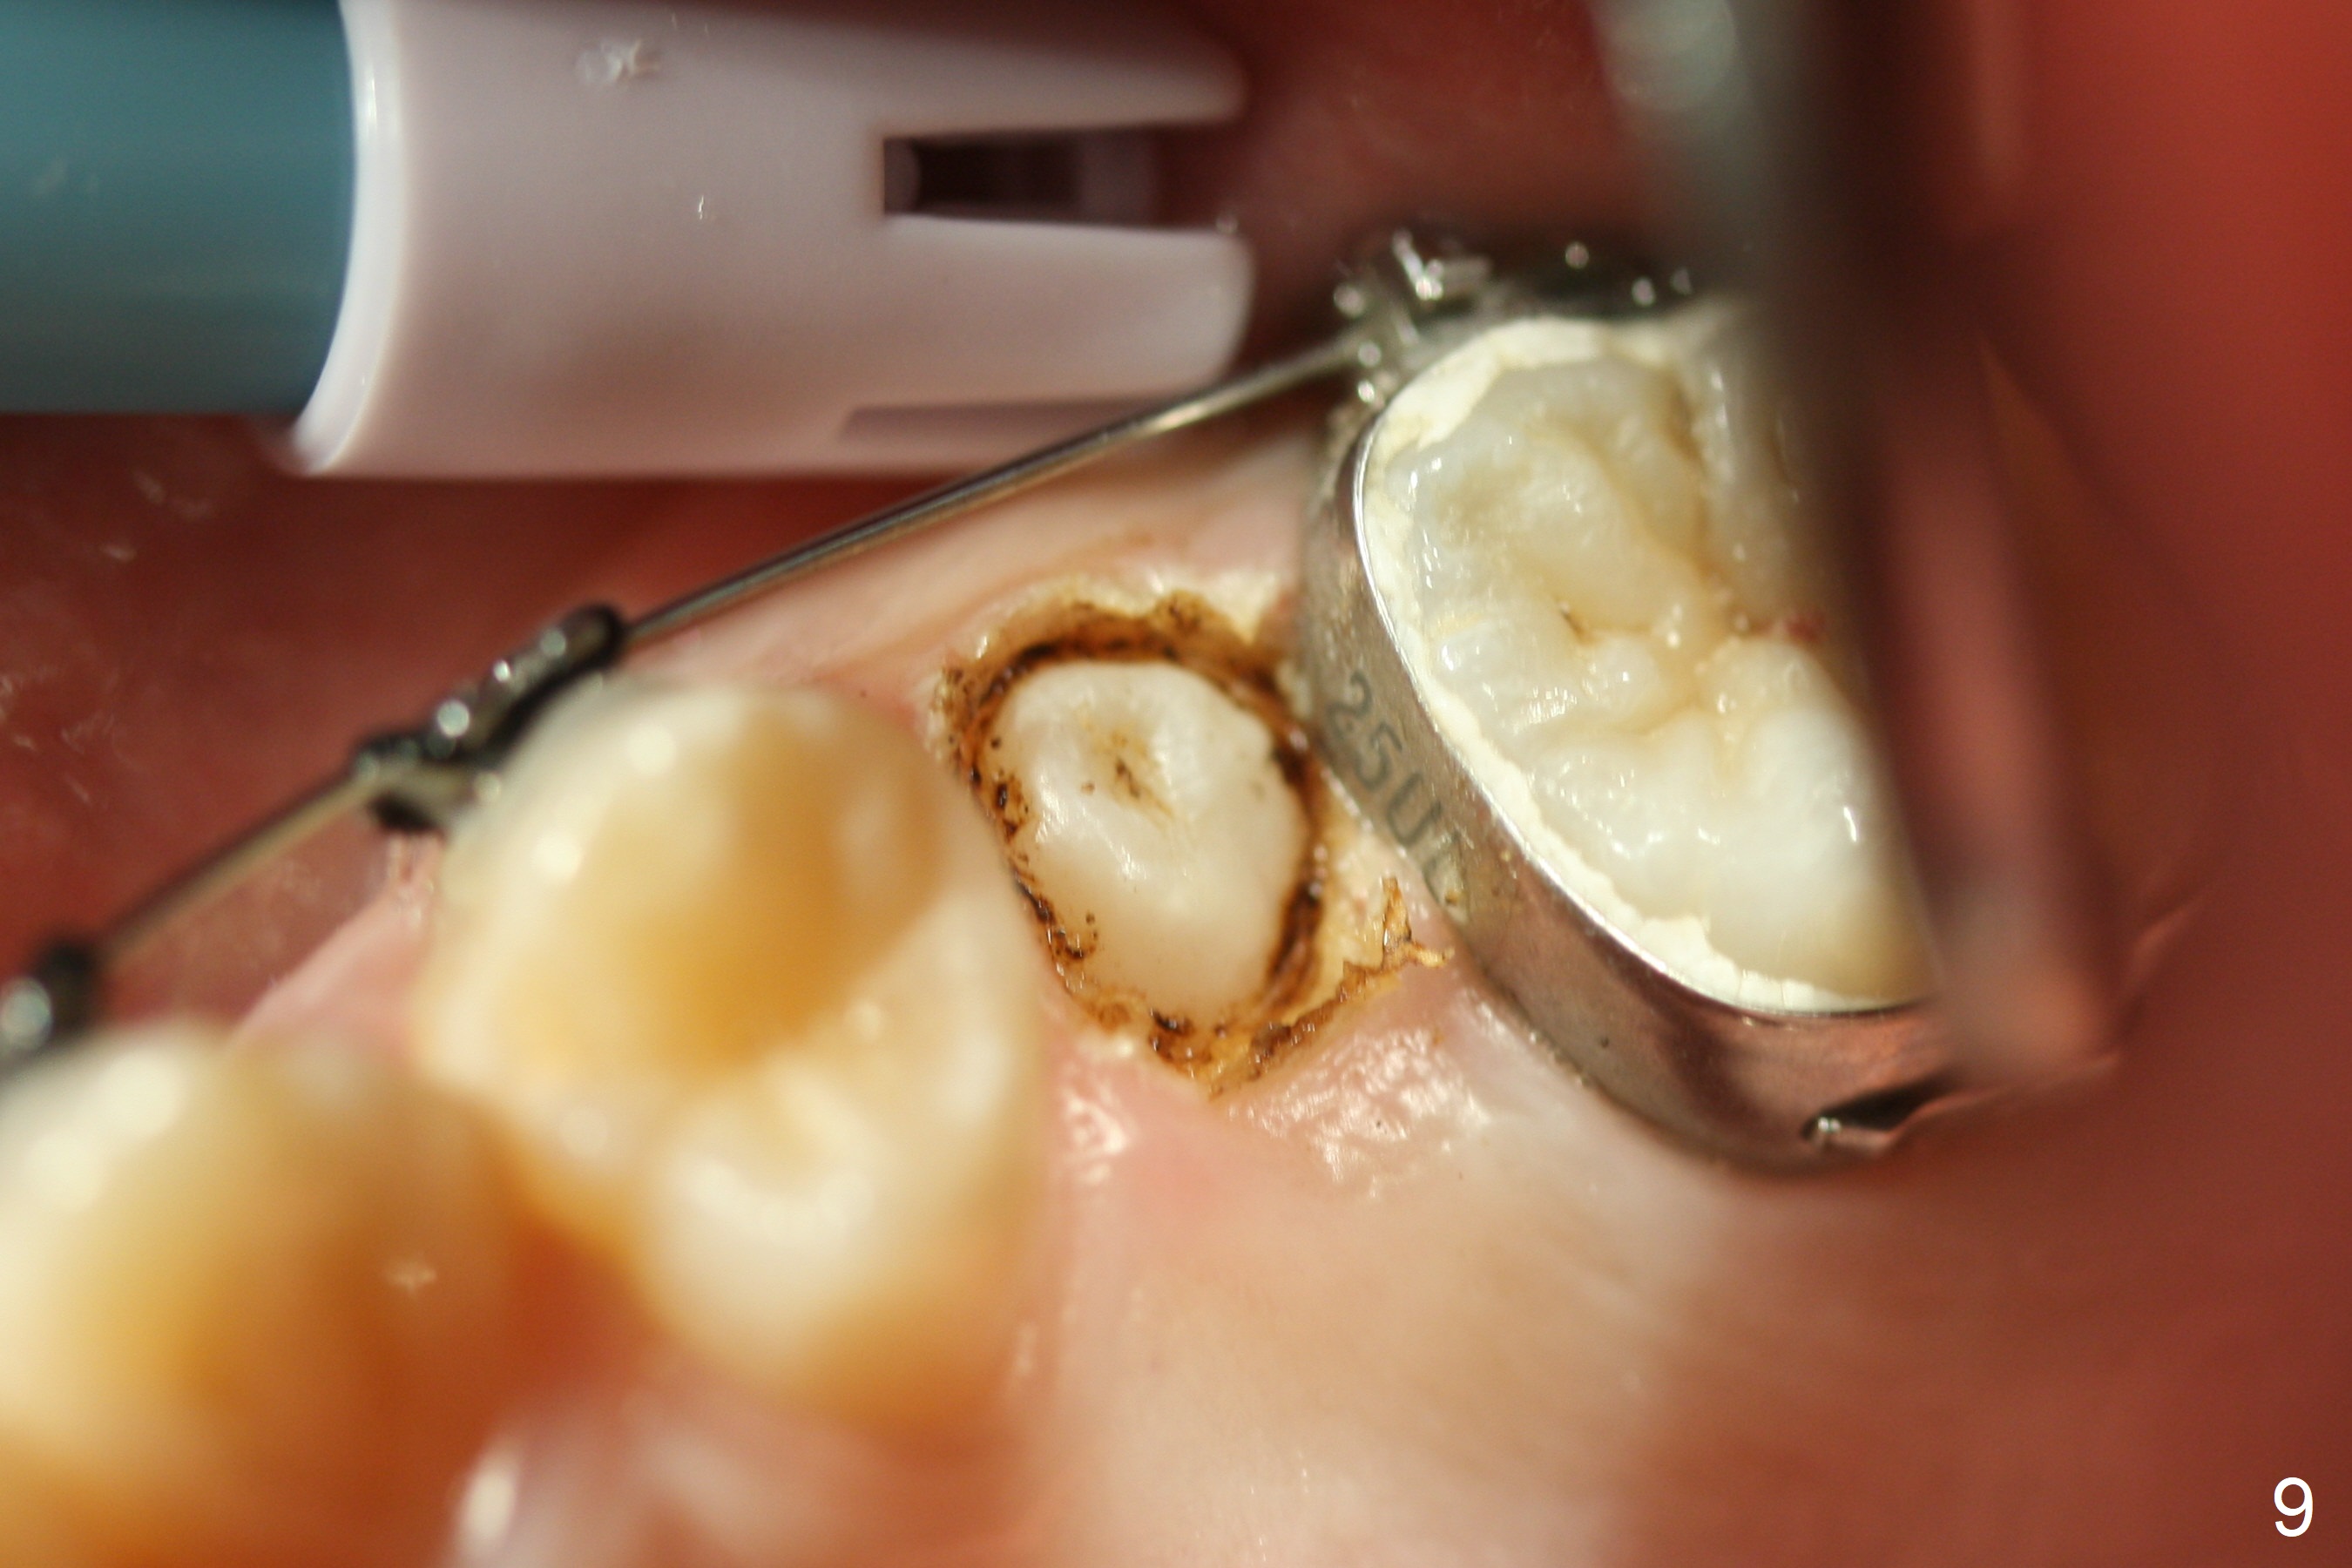

The patient and father do not favor extraction. Five months post extraction of UL E and 2 months post banding (18 ss wires), UL5 is unerupted and subgingival (Fig.8 (palatal view)) and surgically exposed with Diode laser (Fig.9). A retraction tag should have been placed to facilitate eruption. Two weeks later, the tooth is erupting; a bracket is placed. The tooth is apparently erupted 1.5 months later and is no longer engaged to the arch wire.